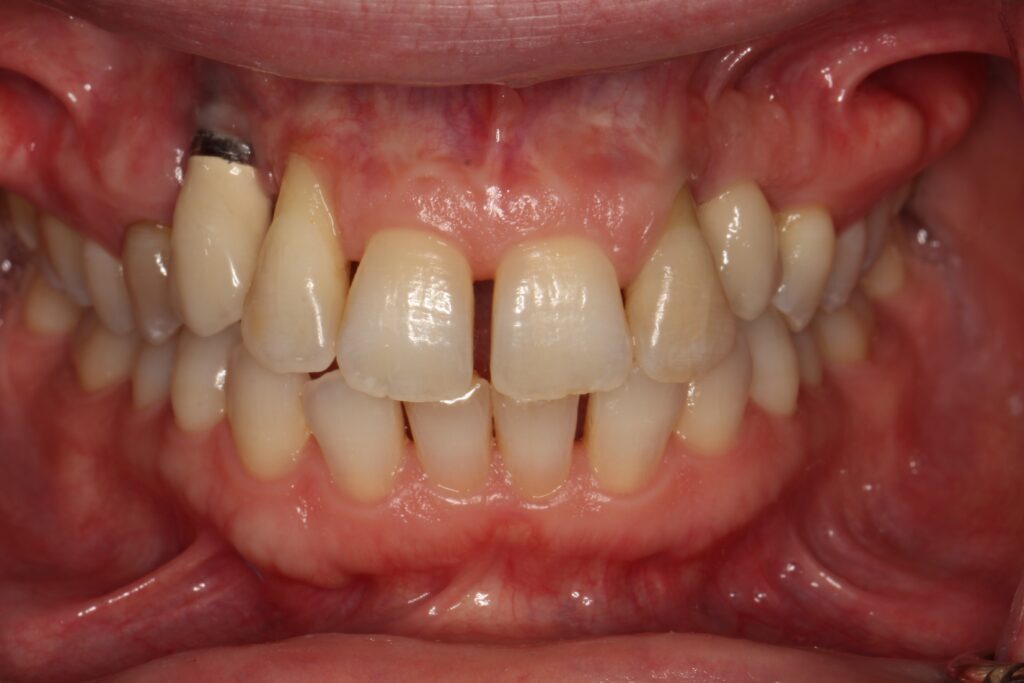

A selection of partial arch fixed implant bridge patients